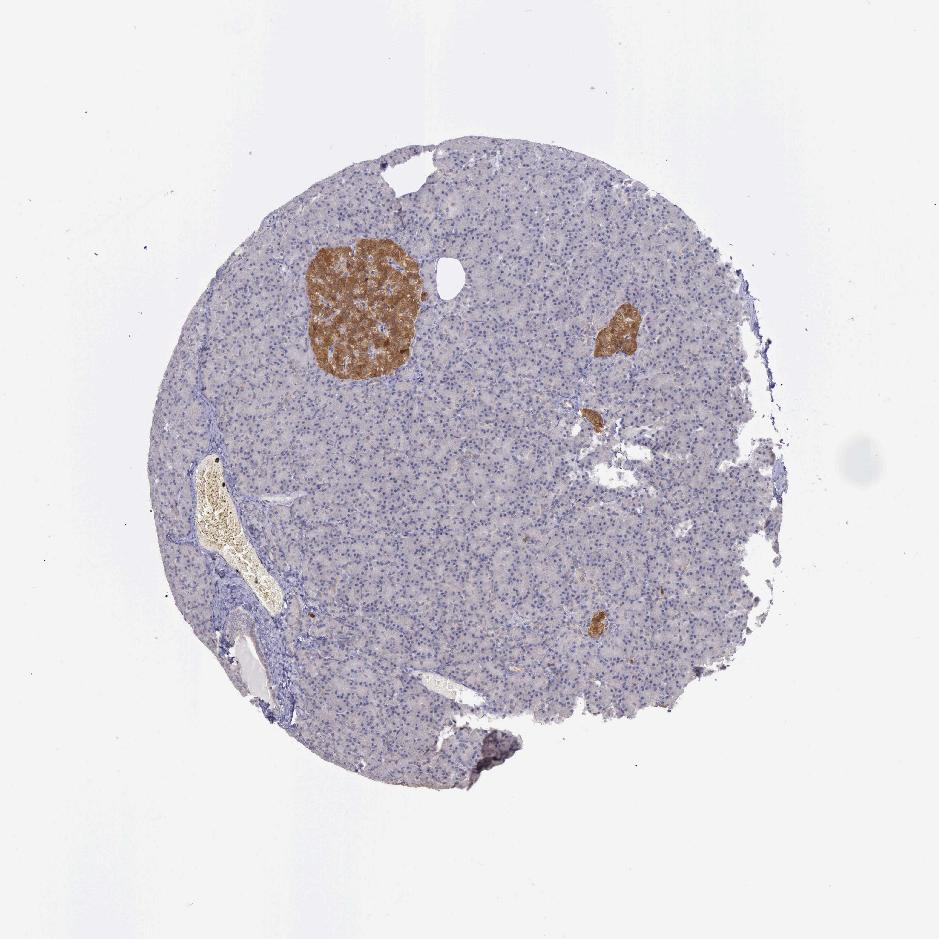

PANCREAS - Antibody stainingi

Antibody staining in the annotated cell types in the current human tissue is reported as not detected, low, medium, or high, based on conventional immunohistochemistry profiling in selected tissues. This score is based on the combination of the staining intensity and fraction of stained cells.

Each image is clickable and will lead to virtual microscopy that enables deeper exploration of all samples and also displays staining intensity scores, fraction scores and subcellular localization as well as patient and tissue information for each sample.

Antibody HPA001208

Exocrine glandular cells Not detected

Pancreatic endocrine cells High